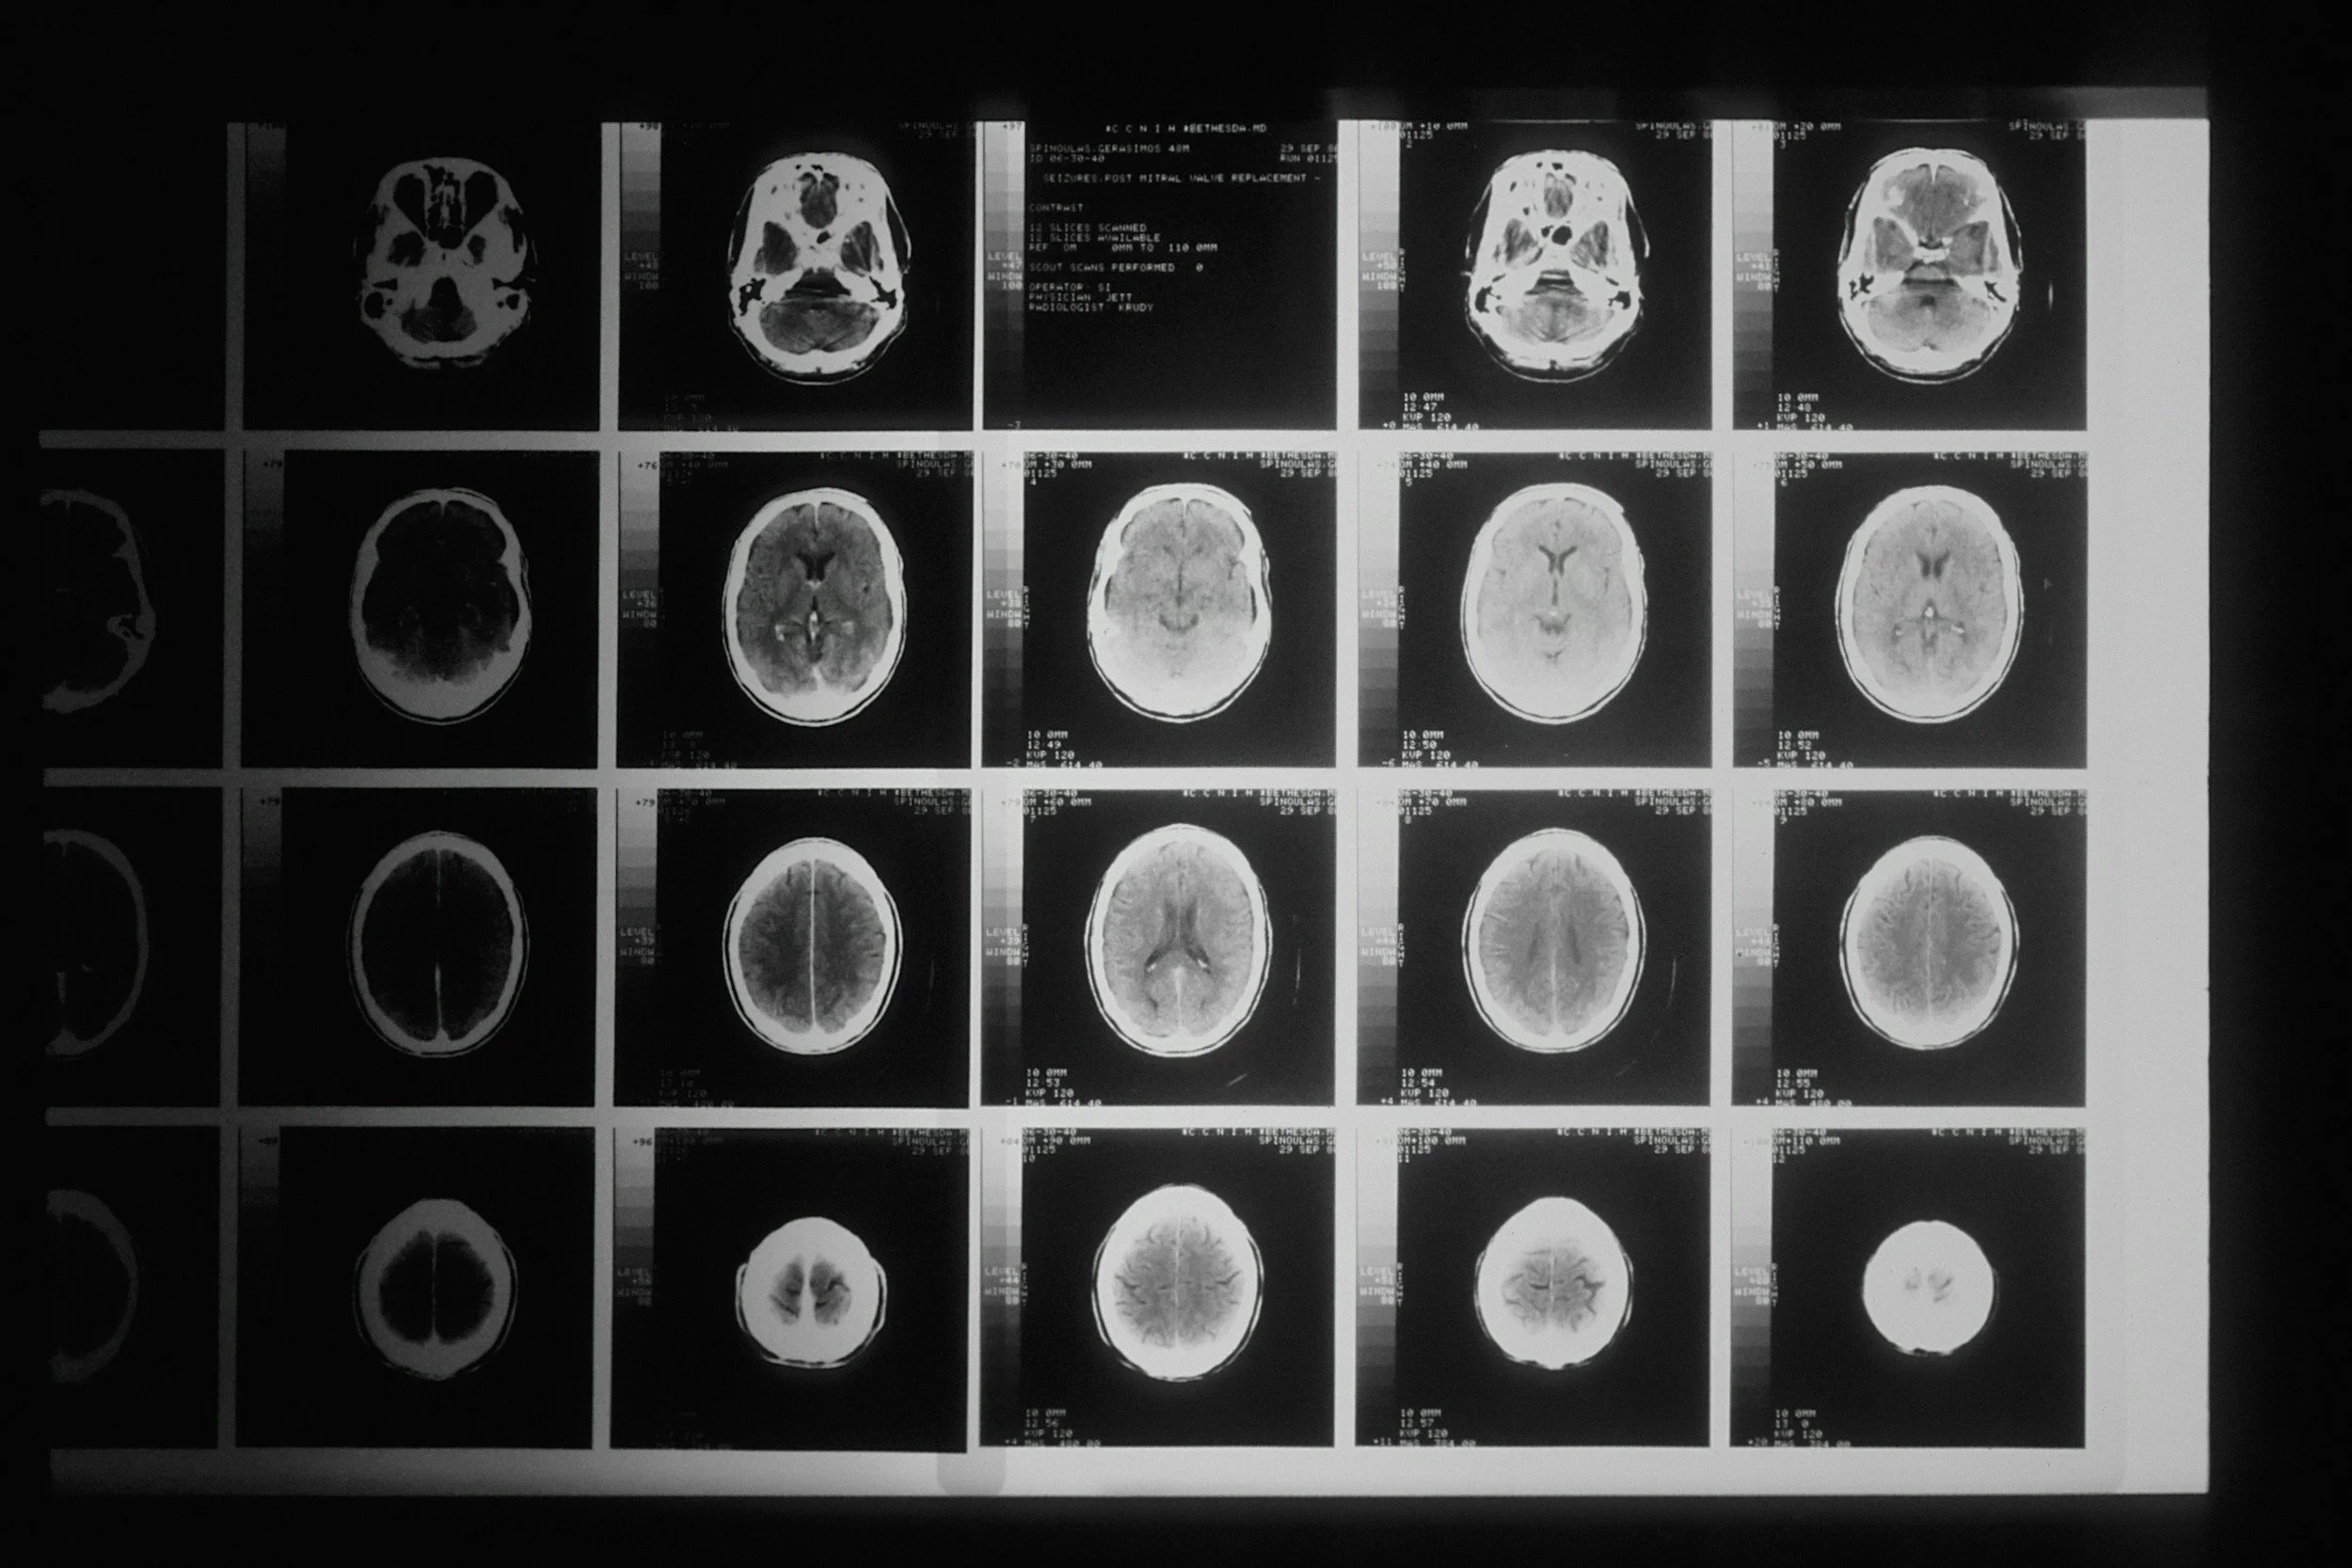

When it comes to something as serious as a neurosurgery diagnosis, it’s normal to want another expert to review the facts. Dr. Ramesh Babu offers a professional second-opinion review. Upload your records and imaging, tell us your questions, and receive a clear written summary based on what you submit.

Dr. Ramesh Babu’s Second Opinion service lets you securely submit your medical records and imaging (MRI/CT reports, notes, test results, and prior treatment history). Dr. Babu will review what you provide and share a clear written opinion that helps you understand:

• MRI/CT imaging reports (PDF)

• Actual imaging files (DICOM) if available